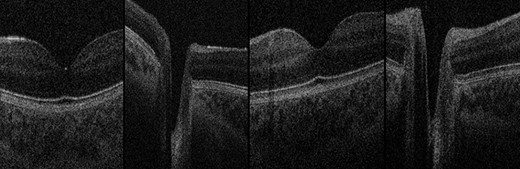

Handheld OCT was also performed using the Envisu C2300 (Leica Microsystems, Wetzlar, Germany) with each twin in the lateral decubitus position (Fig. 4), demonstrating healthy foveae and no optic nerve head swelling (Fig. 5). All OCT parameters fell within the normal range for age [6]. Our OCT acquisition protocol has been recently described [7].

OCT Images. Normal foveae and optic nerve head appearance in both twins, excluding papilloedema. Far-left: Twin 1 normal fovea; centre-left: Twin 1 normal optic nerve head; centre-right: Twin 2 normal fovea; far-right: Twin 2 normal optic nerve head.